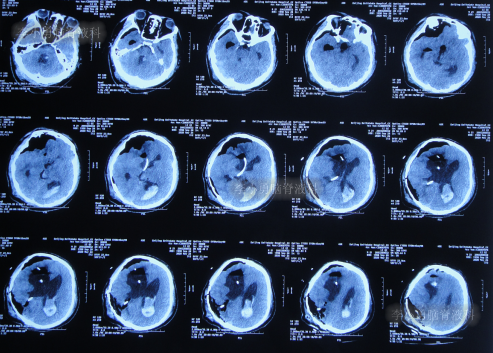

入院时查头颅CT示脑室分流术后状态,脑积水,脑室有积血(图-10)。

图-10:2020年5月20日头颅CT

入院当天进行了原脑室分流管拔除术+脑室外引流术(图-11)。

图-11:2020年5月20日术后头颅CT

脑室外引流术后4天即2020年5月24日下午13点,患者呕吐加重,查头颅CT示出血增多(图-12)。

图-12:2020年5月24日下午13点半头颅CT

当天晚上加做了脑室外引流术,术后当晚查头颅CT示脑室引流术后状态(图-13)

图-13:2020年5月24日晚上20点头颅CT

2020年5月30日(入院治疗10天),查头颅CT示脑室缩小,积血减少(图-16),体温变正常。

图-16:2020年5月30日头颅CT

2020年6月4日(入院治疗15天),查头颅CT示积血进一步减少(图-17)。

图-17:2020年6月4日头颅CT